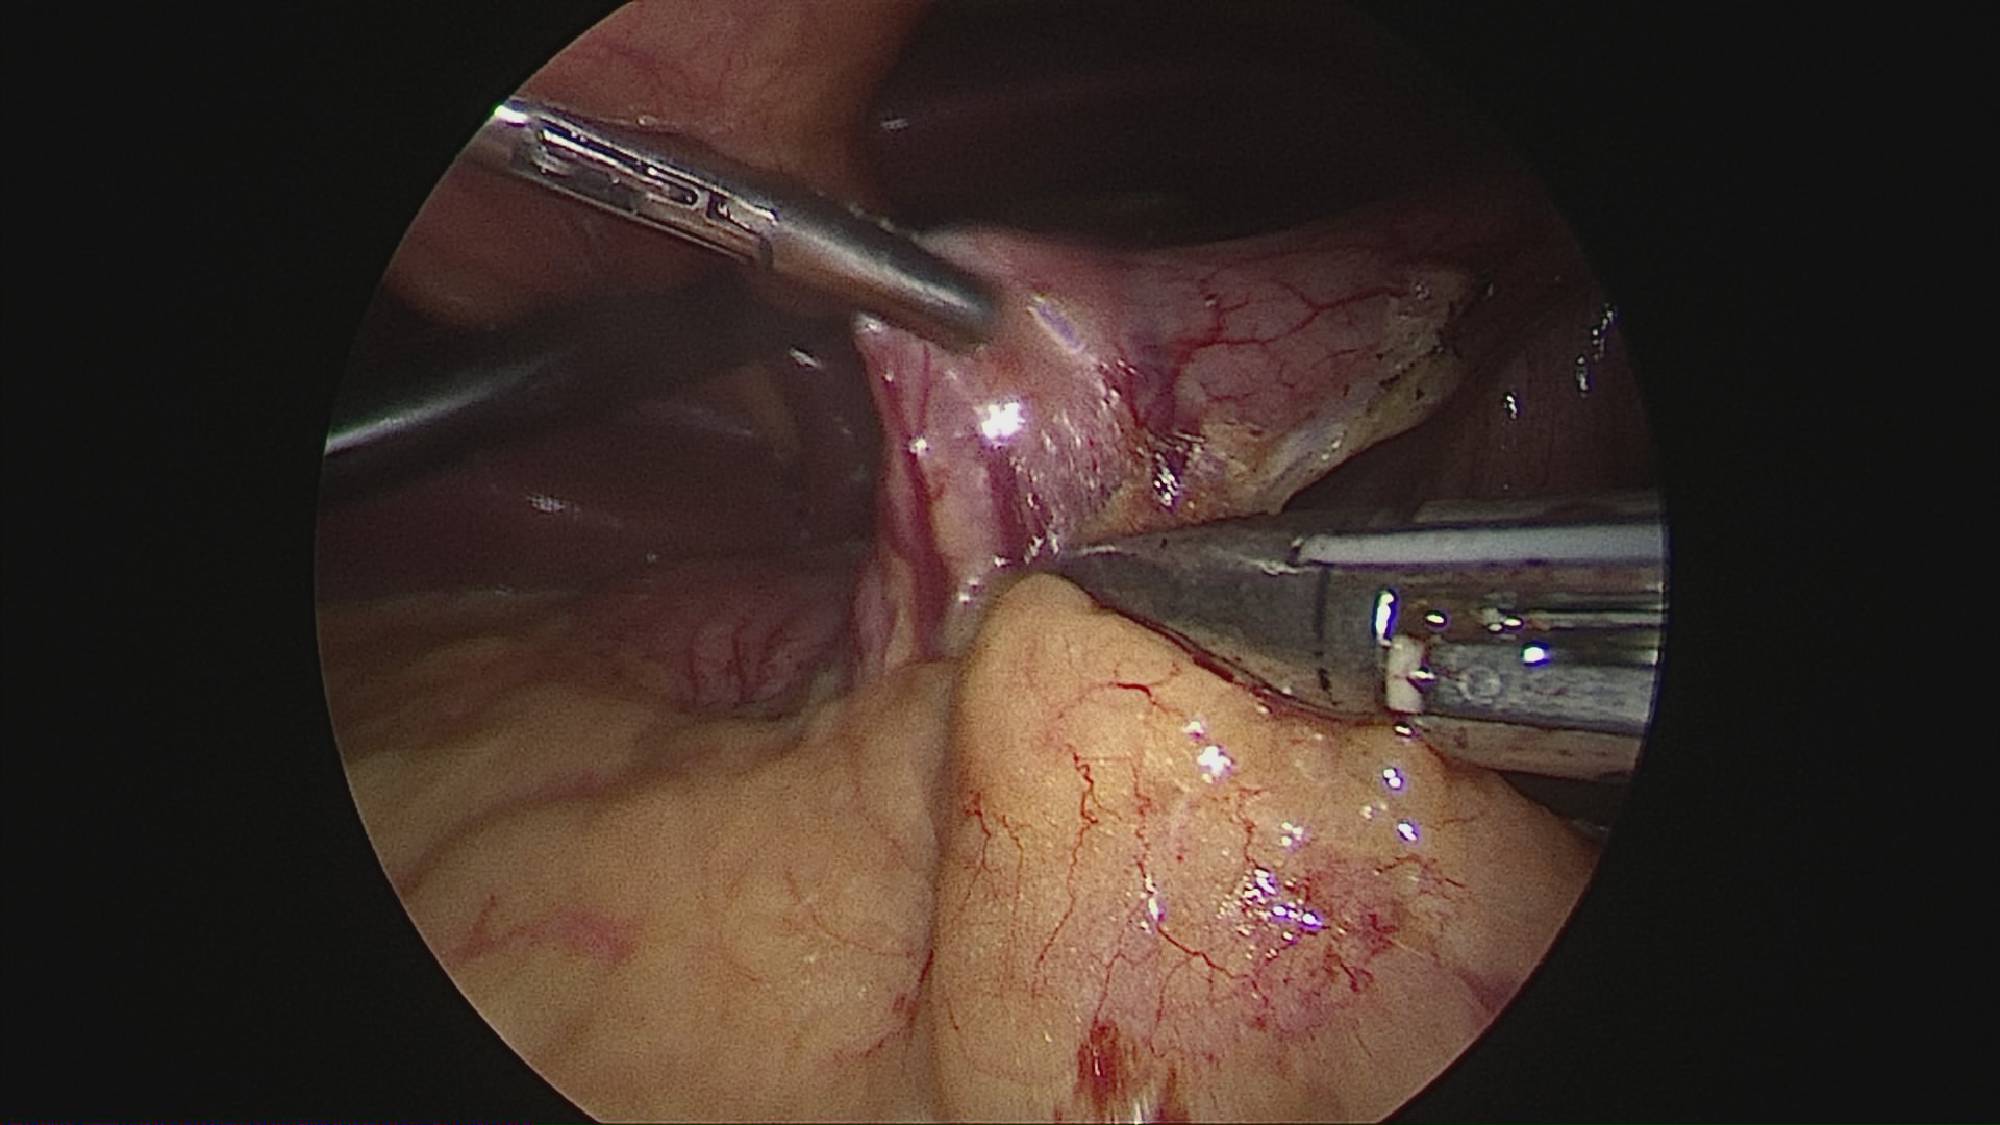

Operația ”de micșorare a stomacului” se realizează miniminvaziv (laparoscopic) și constă în îndepărtarea marii curburi gastrice cu păstrarea antrului gastric și a micii curburi sub forma unui tub calibrat pe o sondă.

Tehnica aduce beneficiile chirurgiei laparoscopice, durere redusă, externare în primele 48 ore de la intervenție. Avantajul său constă în confortul oferit pacientului care prezintă senzația de sațietate rapid prin umplerea unui stomac de doar 100 ml, reducerea senzației de foame prin suprimarea secreției de grelina. De asemenea, nu modifică traseul alimentelor, nu exclude segmente digestive din circuit și pierderea excesului ponderal poate ajunge până la 100%.